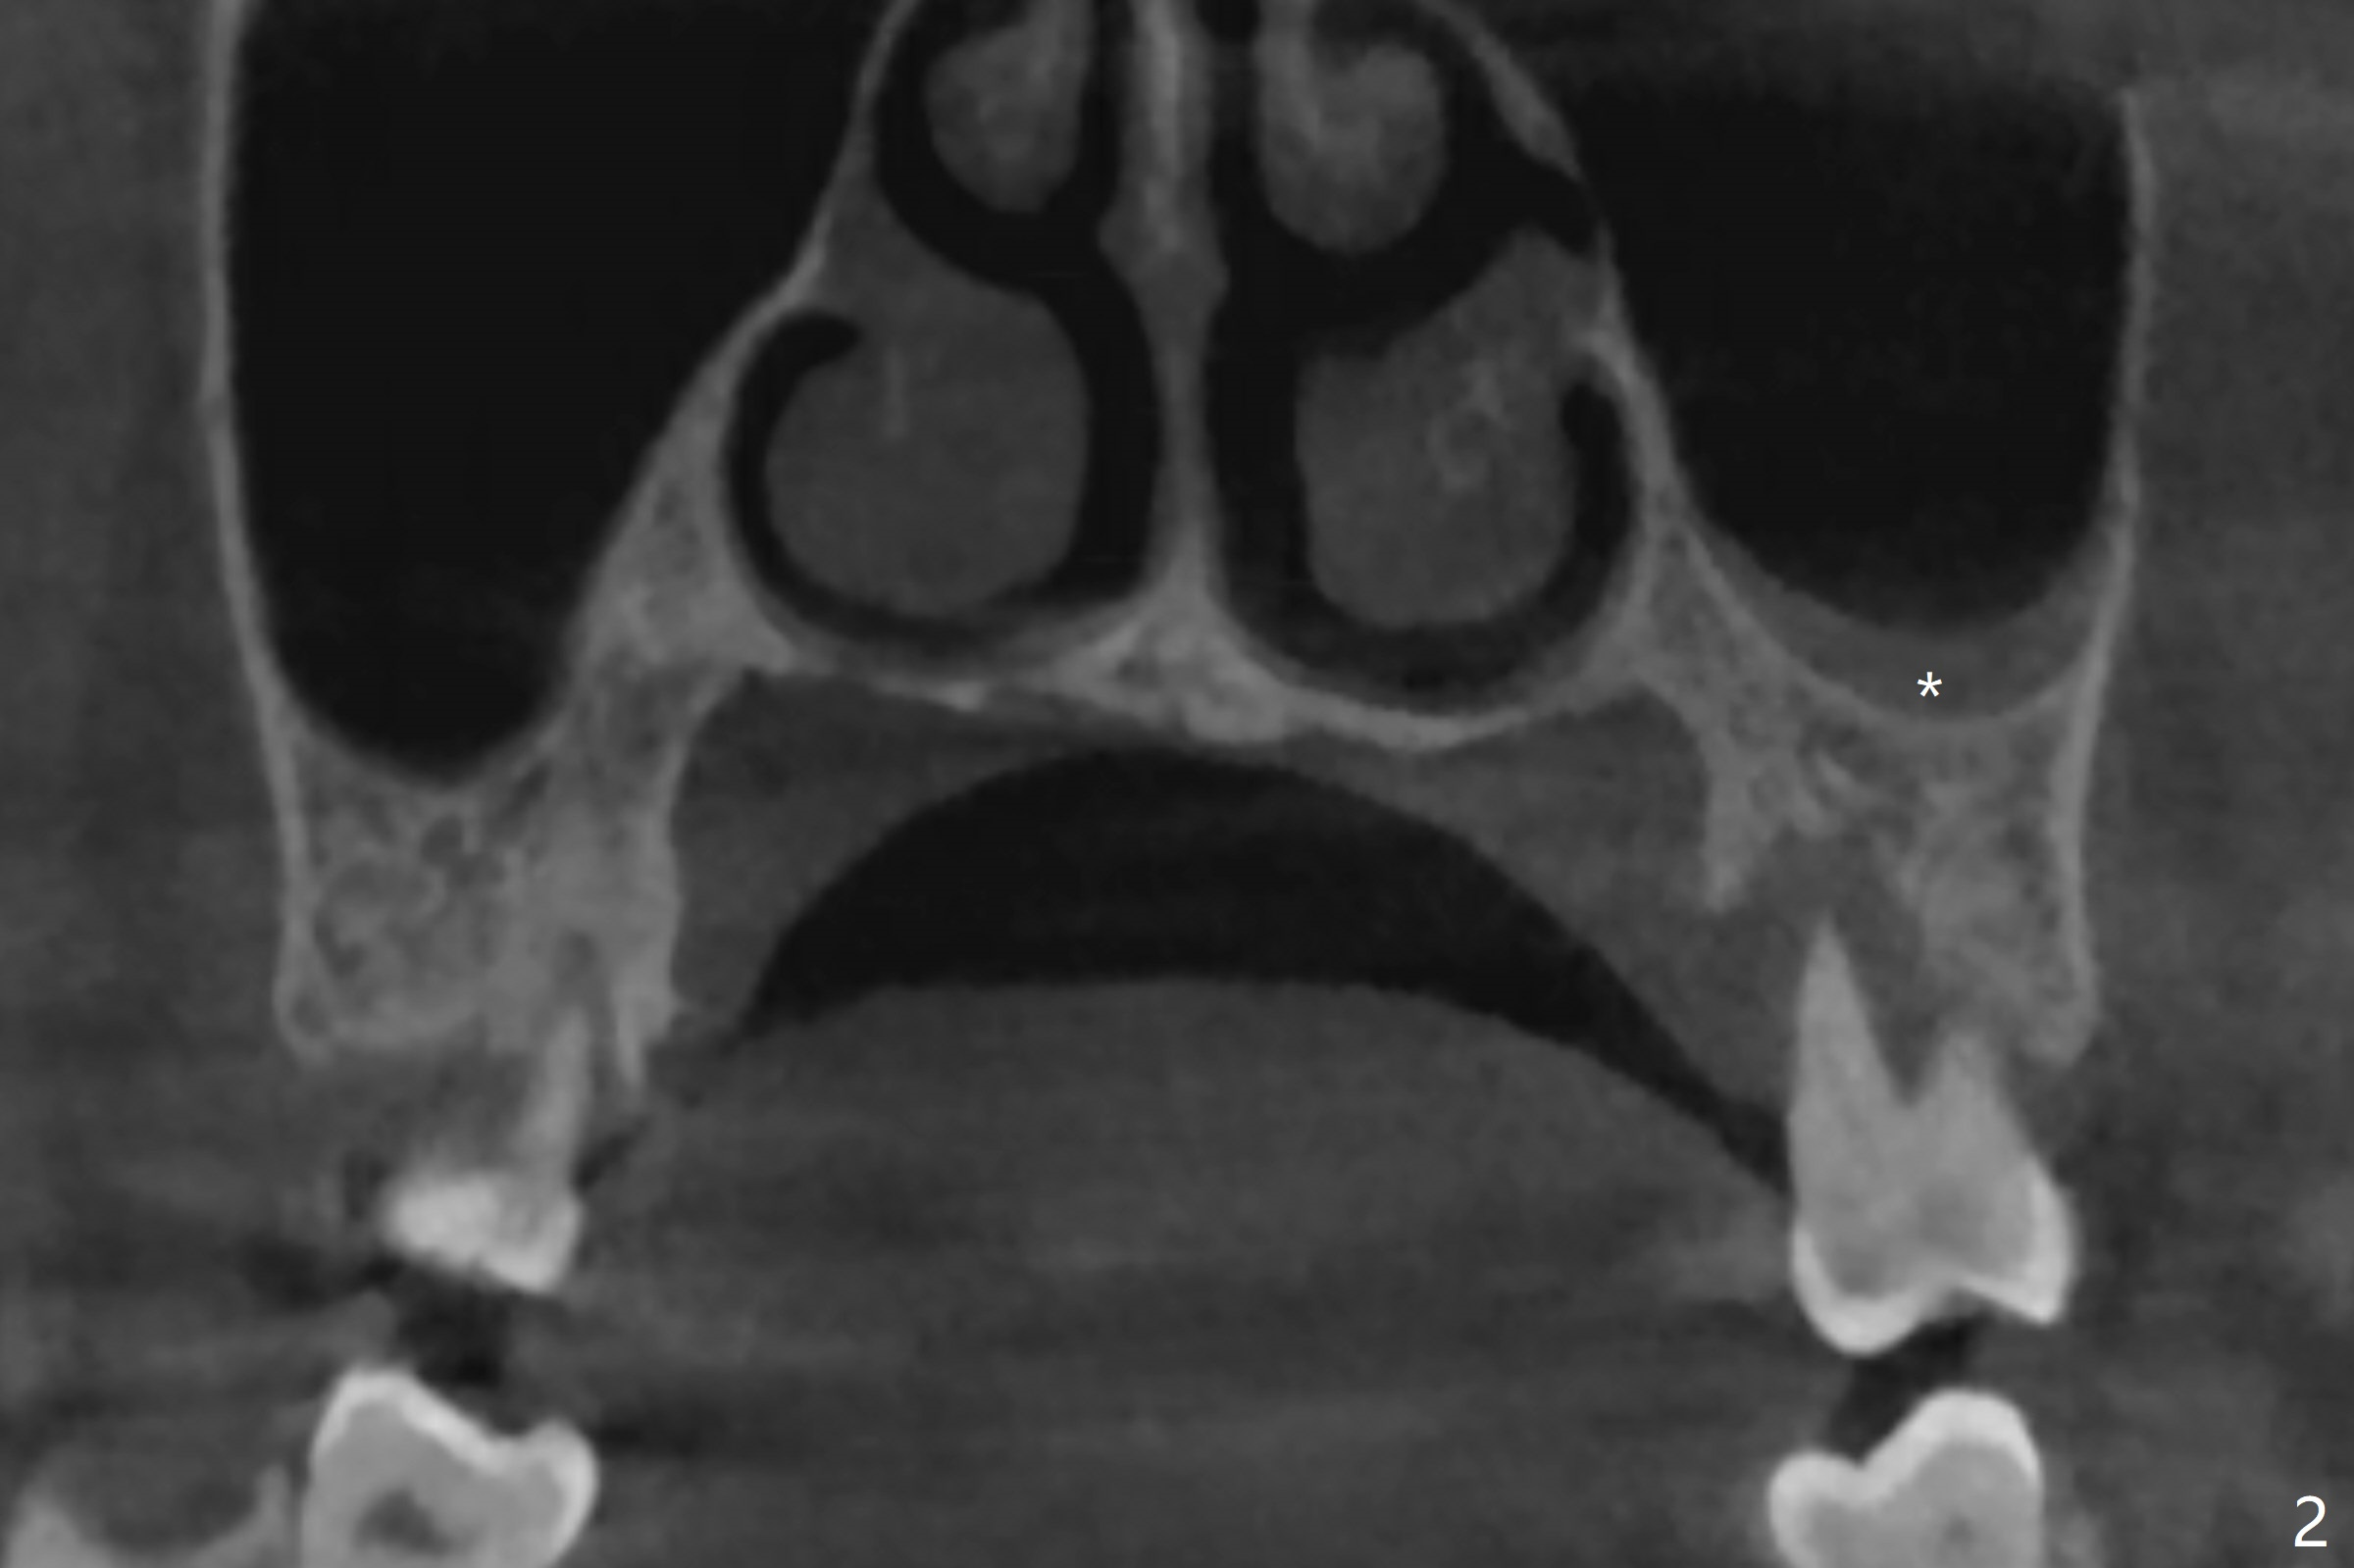

The 54-year-old woman (bruxer) agrees to have implant because of the loose tooth at #15 (Fig.1 (pan)). Since the left sinus membrane is thickened (Fig.2 *), an immediate implant will not be penetrated the sinus floor if primary stability is acceptable. If the sinus lift has to be done, PRF membrane/plug will be prepared. The large periradicular radiolucency is associated with the vertical palatal root fracture (Fig.3). A 5x8.5 mm implant is placed as buccal as possible with guide (Fig.4).